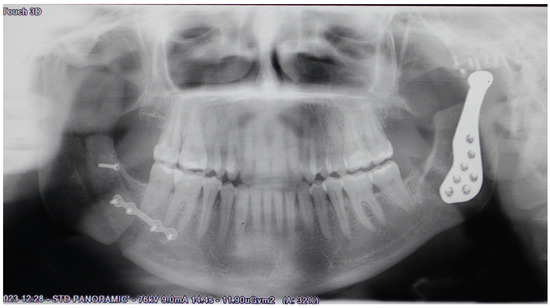

| Gender/Age (Years) | Image | MIO Preop (mm) | MIO at 6 Months (mm) | VAS Preop | VAS at 6 Months | Functional Result | Aesthetic Result | Complications |

|---|---|---|---|---|---|---|---|---|

| F/36 | ![]() | 25.9 | 36.4 | 8 | 3 | 2 | 2 | None |

| F/49 | ![]() | 15.6 | 35.4 | 9 | 4 | 2 | 2 | Partial left facial palsy |

| F/68 | ![]() | 30.5 | 40.3 | 8 | 3 | 2 | 2 | None |

| F/42 | ![]() | 26.4 | 33.5 | 7 | 2 | 2 | 2 | None |

| Average | 24.6 | 36.4 | 8 | 3 | 2 | 2 |